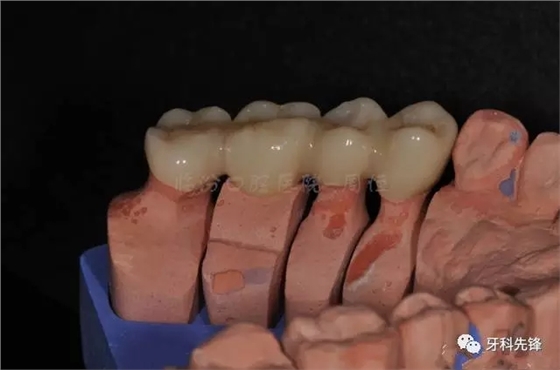

圖13牙體預(yù)備模型照

640.webp (17).jpg